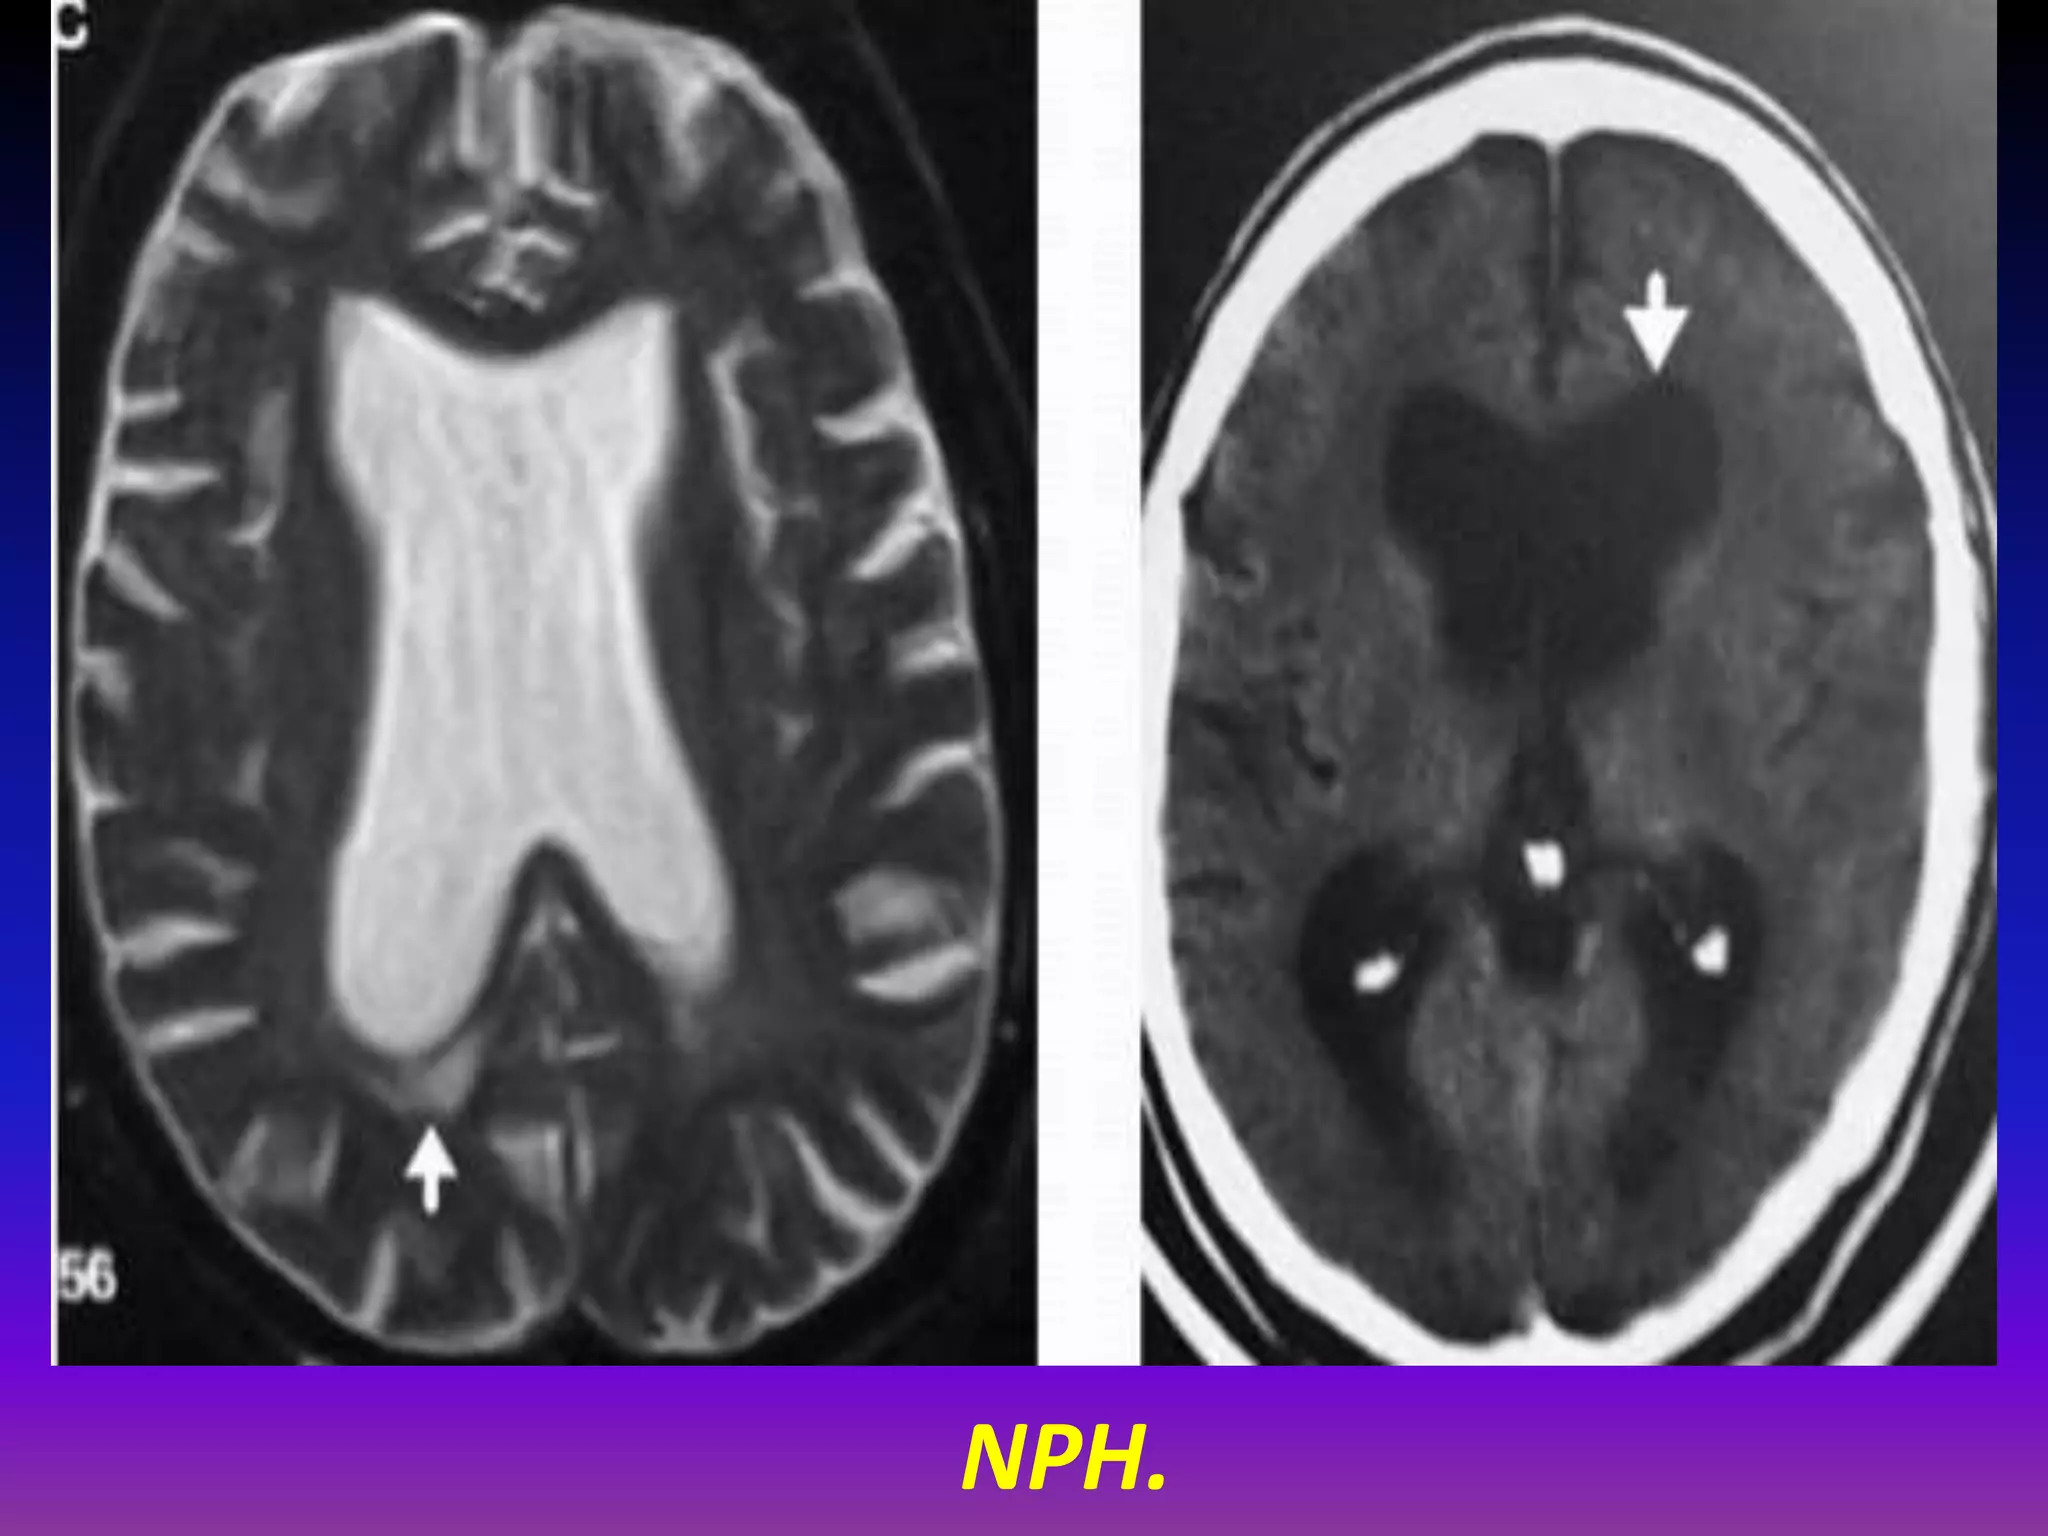

NPH.

CSF Flow Void.

• CSF flow void is useful indicator of favorable

response to CSF diversion